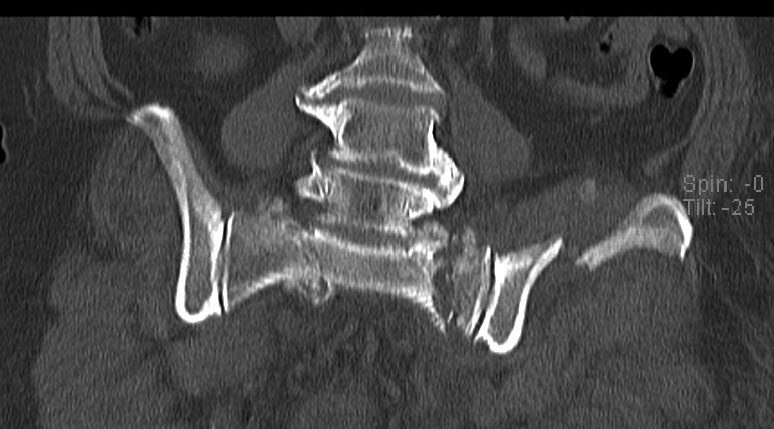

Уважаемые коллеги, в продолжении обсуждения перелома костей таза с отрывами остей досылаю R-снимки (КТ и КТ с 3d реконструкцией)

Имя     : стриганова TB3 1.jpg